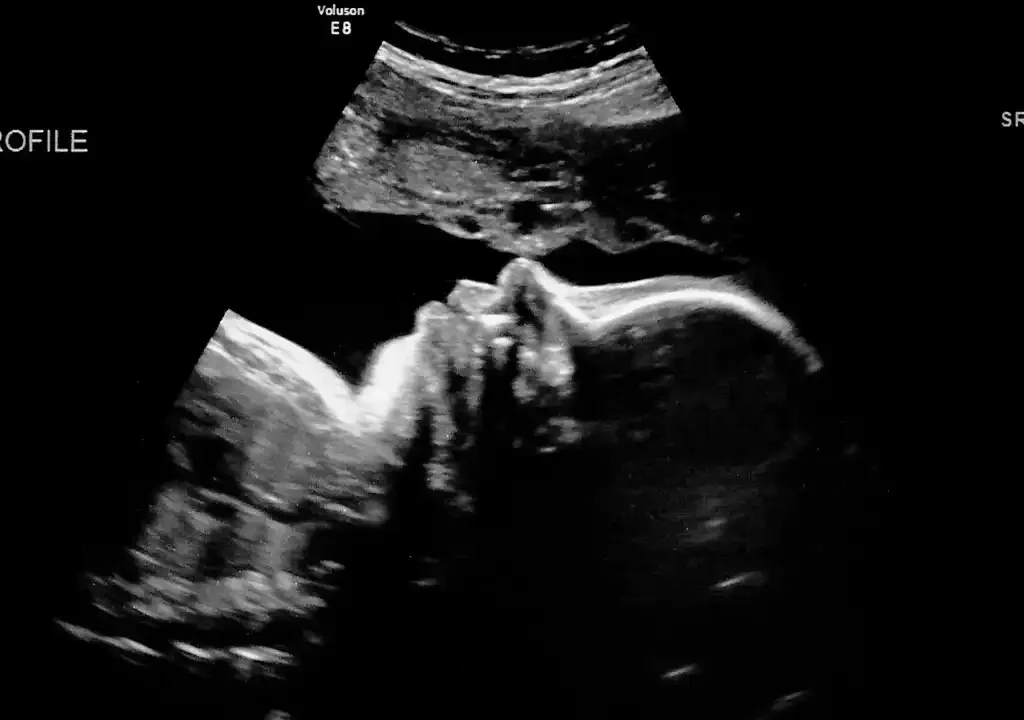

سونوگرافی ماه پنجم بارداری (هفته ۱۸ تا ۲۰)

سونوگرافی که بین هفتههای 18 تا 20، انجام میشود، یکی از مهمترین بررسیهای بارداری به شمار میرود. هدف این سونوگرافی، ارزیابی جامع ساختار بدن جنین، موقعیت جفت، رشد مناسب اندامها و بررسی برخی اختلالات احتمالی است. این مرحله برای اطمینان از سلامت مادر و جنین نقش کلیدی دارد. در ادامه شما را بیشتر با این سونوگرافی آشنا میکنیم.

چکاپ ساختار قلب، مغز، ستون فقرات

در این سونوگرافی، پزشک با دقت قلب، مغز، نخاع، ریهها، معده، کلیهها، مثانه و استخوانبندی جنین را بررسی میکند. در واقع، ساختار چهار حفرهای، جریان خون و ضربان منظم قلب، اندازه، شکل و تقسیمبندی نواحی مختلف مغزی و انحنای صحیح ستون فقرات مورد ارزیابی قرار میگیرد. این ارزیابیها به تشخیص زودهنگام ناهنجاریهای ساختاری و در مواردی، تصمیمگیری بهموقع درباره ادامه روند بارداری کمک میکند.

تشخیص موقعیت جفت (پلاسنتا) و میزان مایع آمنیوتیک

در این سونوگرافی، موقعیت جفت مشخص میشود. آگاهی از جایگاه جفت، به تشخیص خطرات احتمالی مانند خونریزی یا محدودیت رشد جنین کمک میکند. همچنین میزان مایع آمنیوتیک بررسی میشود که نقش حیاتی در رشد و حرکت جنین دارد. کم بودن یا زیاد بودن مایع میتواند نشانهای از مشکلات جنینی یا جفتی باشد و نیاز به پیگیریهای بعدی دارد.

احتمال تعیین جنسیت جنین

اگر جنین در وضعیت مناسبی قرار گرفته باشد، در سونوگرافی آناتومی معمولا جنسیت با دقت نسبتا بالا قابل تشخیص است. بااینحال، تعیین قطعی جنسیت به وضعیت قرارگیری جنین و تجربه سونوگرافیست بستگی دارد. بعد از تعیین قطعی، میتوانید برای جشن تعیین جنسیت نوزاد اقدام کنید.